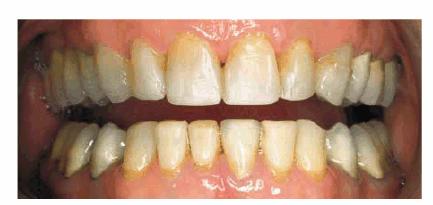

Age and dysfunctional habits can contribute to severe wear over the years. Figures 29-10A, and 29-10B demonstrate evidence of bruxism in an 86-year-old

woman who had been advised to wear a bite guard when she was in her mid 50s.

She disappeared from the practice and returned 30 years later demonstrating

severe wear, loss of vertical dimension, loss of masticatory function, and

temporomandibular pain. More importantly, she was embarrassed by her smile. Her

treatment plan consisted of a temporary crown and bridge to restore vertical

dimension and comfort. She was subsequently treated months later with fixed prosthodontics

using metal-ceramic restorations (Figure 29-10C). She regained much of her self-confidence, as

well as masticatory function, following the esthetic reconstruction of the

maxillary arch (Figure 29-10D) and planned to restore the lower arch.

Figure 29-10A: This lady presented with a severe bruxism habit that resulted in virtually all of her maxillary teeth being hidden when she smiled.

Figure 29-10B: Although she was advised more than 30 years previously to wear a night guard, she chose not to do so.

Figure 29-10C: Crown lengthening followed by prosthodontic reconstruction helped to recreate her smile. The next step is for her to rebuild the mandibular arch.

Figure 29-10D: The reconstructed teeth of this 88-year-old lady now enhance her smile.